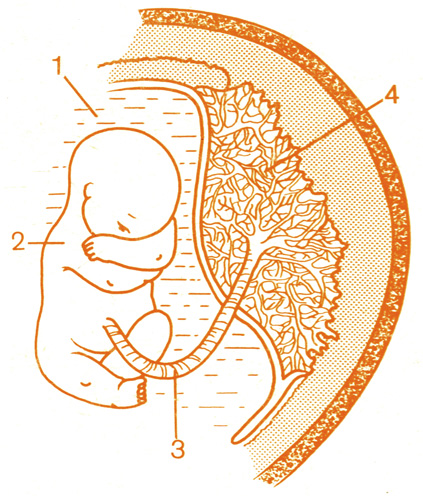

Околоплодный пузырь и плацента: структура и функции